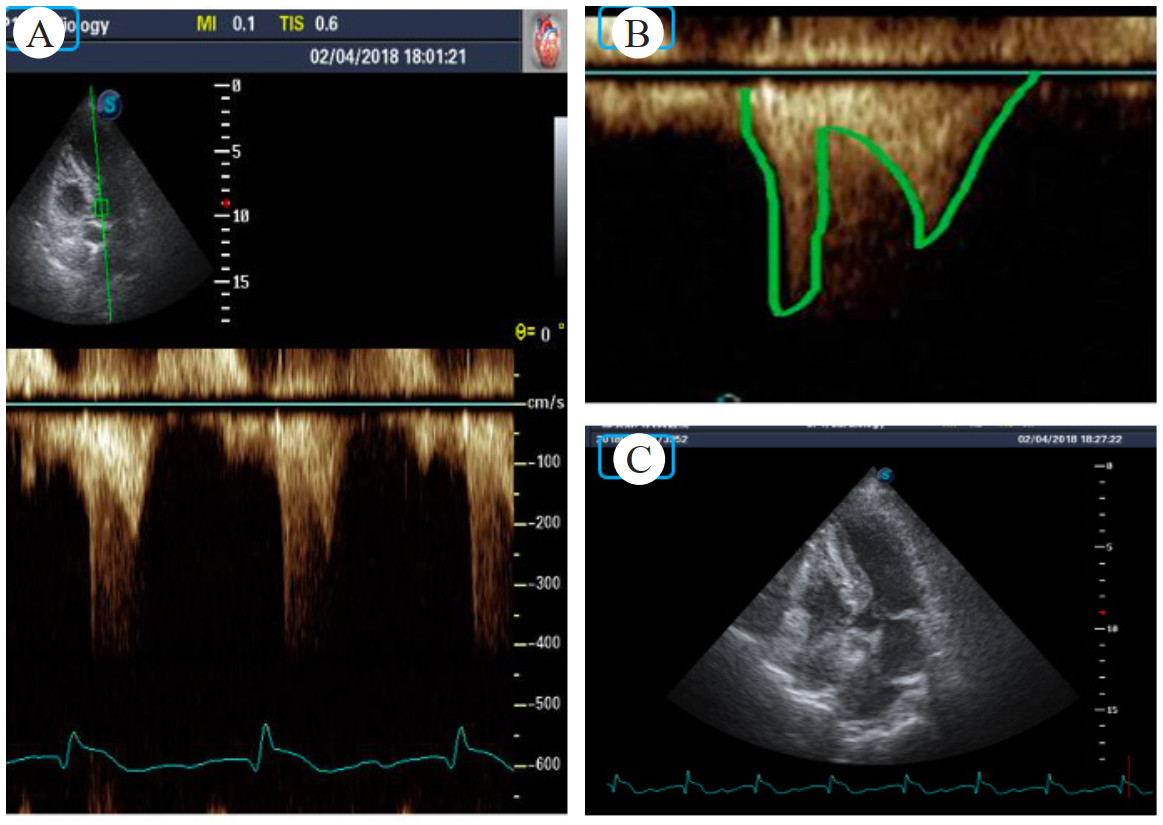

| A: 胸骨旁长轴左心室明显增厚; B: 胸骨旁长轴室间隔和升主动脉夹角; C: 心尖4腔心左室流出道血流速增快; D: 正常患者室间隔和升主动脉夹角 图 3 病例2的超声检查结果 |

DLVOTO发病主要机制有两种:(1)二尖瓣部分装置收缩期向左室流出道移位;(2)左室心肌收缩力随药物、运动、心脏前后负荷的改变而改变,其梗阻程度是不固定的[3]。因此DLVOTO常合并SAM征,继而导致二尖瓣反流,从而诱发血流动力学不稳定[4]。研究证实DLOVTO患者91%有SAM征,61%患者为严重SAM,即室间隔与二尖瓣前叶或键索接触,如图 3病例2情况。44%患者有中度以上二尖瓣反流[8]。86%患者表现为左心室较小[左心室舒张末内径(41±6)mm,收缩末内径(24±5)mm];还有左心室不对称性肥厚[室间隔(16±4)mm,左心室后壁(12±3)mm];左心房轻度扩大[左心房内径(42±9)mm;左心房面积指数(24±6)cm2/m2];以及左心室高动力[左心室射血分数(74±9)%]等表现[8]。本文中两例患者均有SAM征,无二尖瓣反流;病例1基底部室间隔为13 mm,左室后壁13 mm;病例2底部室间隔为12 mm,左室后壁11 mm。而且两例患者左心室高动力表现(左心室射血分数分别为58%和72%),均在使用多巴酚丁胺后诱发DLVOTO。而超声科报告中提示患者左心室收缩功能正常,常误导诊断。

此外还需注意基底部室间隔肥厚,主要在既往有高血压病史老年人,心脏超声表现为单纯S型室间隔肥厚(基底部室间隔≥14 mm,基底部/中部室间隔≥1.3)。由于左心室和升主动脉夹角增大(图 3),有可能诱发动态梗阻性基底部室间隔肥厚;表现为(1)劳累后呼吸困难,接近晕厥和胸部不适等左室流出道梗阻表现;(2)运动后LVOTG > 30 mmHg;(3)经β受体阻滞剂或其他负性肌力药物治疗后症状改善[11]。本文两位都有高血压病史的老年患者,因此考虑长期高血压导致左心室和升主动脉夹角增大是患者本次发病诱因之一(图 3)。